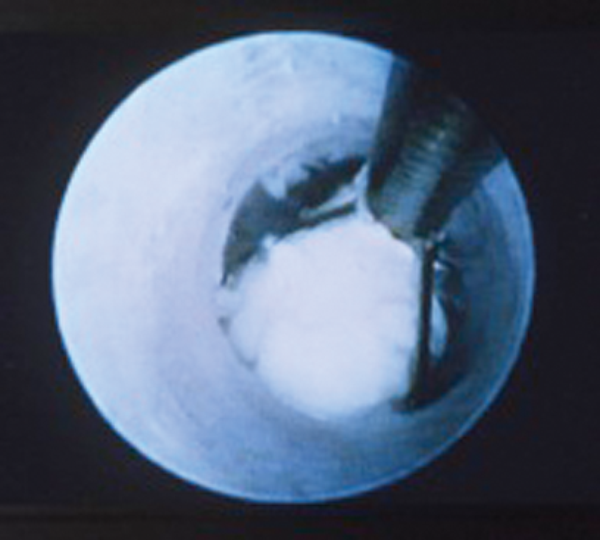

Minimally invasive techniques for benign salivary gland obstruction

Salivary gland obstruction is a common condition – it is recognised by a complaint of intermittent meal-time swelling of the affected salivary gland and can be accompanied by recurrent infections. Imaging can identify the nature and location of an obstruction...